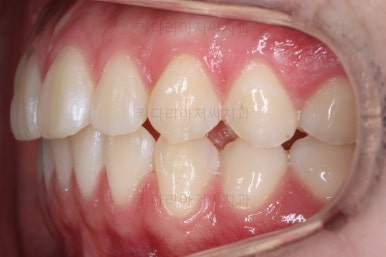

각각 왼쪽, 오른쪽의 교합의 모습입니다.

가장 좋은 교합은 위아래 치아들이 지그재그로 톱니바퀴 물리듯이 맞아들어가야 하는데 오른쪽 사진들 보면 중간중간 빈틈도 많이 보여요.

이런 교합은 장기적으로 치아 수명을 단축시킬 수 있습니다.